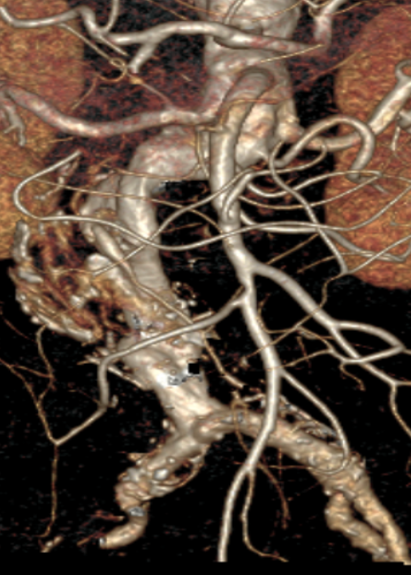

患者男,73岁,因“发现腹主动脉瘤3年余”入院。既往高血压、糖尿病史,长期吸烟。术前CTA显示肾下腹主动脉瘤,近端瘤颈充足,左侧髂内动脉狭窄,右侧正常。

手术采用腹主分支支架,主体释放后行交叉腿髂支延伸。

★ 病例2:右髂外动脉闭塞,保留左侧通畅髂内动脉

患者女,66岁,腹主动脉瘤合并右髂外动脉闭塞。术中开通右侧髂外动脉,封堵右侧髂内动脉,保留左侧通畅髂内动脉。

回顾分析了2013年1月至2022年7月接受EVAR并处理髂内动脉的患者,按血供保留方式分为三组:单侧髂内动脉血供组(单侧血供组,UP)、保留双侧髂内动脉血供组(双侧血供组,BP)和未保留髂内动脉血供组(无血供组,BE)。